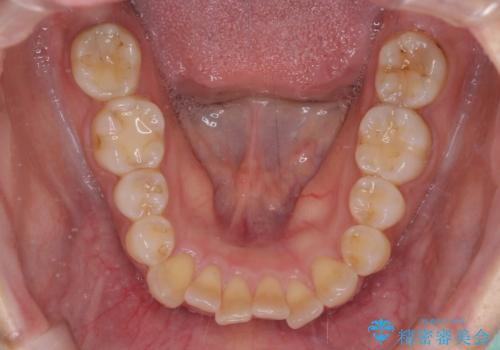

- 上顎の八重歯と全体的なデコボコを気にして来院された患者様です。

口元の突出感はなかったため非抜歯矯正での対応となりますが、八重歯を改善する際に上顎前歯が前突する可能性があったため、上顎臼歯部にアンカースクリューを使用して、歯列が前方に転位しないようにすることとしました。

また舌のトレーニングを行うことで、上顎前歯の突出予防や上下前歯に隙間ができなくなるようにしました。